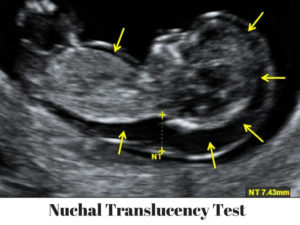

Nuchal translucency scan (NT scan)

The NT scan is an ultrasound that looks at the neck of the baby. It measures a layer of fluid that all babies have at the back of their neck. When the there is more fluid, there is a higher chance that the baby might have Down syndrome.

The NT scan is done between week 11 and week 13 of pregnancy. It is often done with serum screening. Out of 100 babies with Down syndrome, this type of prenatal screening will find about 85.

If your NT is positive, your doctor will offer you NIPT and/or prenatal diagnosis.

The NT scan can also detect signs of trisomy 18 and trisomy 13 and heart defects.

Other body features of the fetus also provide useful information at this point. For instance, the absence of a nose bone is also an indicator for a higher probability of trisomies. In addition, some organs can be visualized, the heartbeat can be heard, and the fetus can be measured to monitor fetal development.